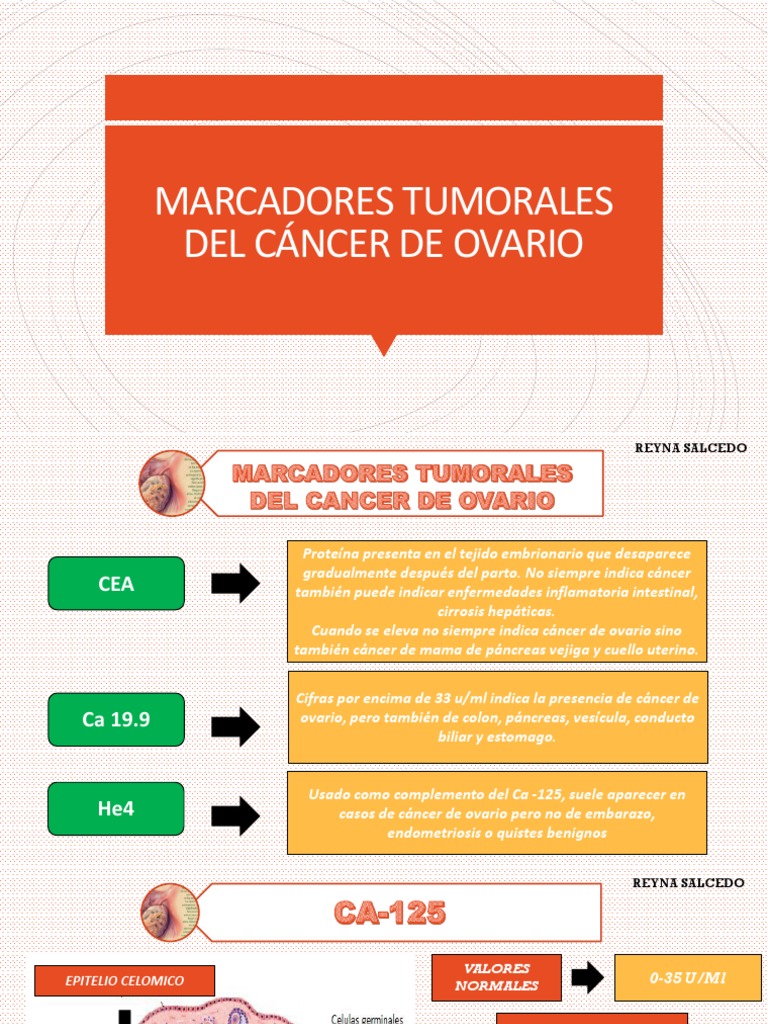

testimonio Instalaciones Para exponer Marcadores Tumorales y Cáncer de Ovario - Instituto de Bioquímica Clínica

Psicologicamente Shinkan danza Marcadores Tumorales - Marcadores de tumores NCI Puntos clave Los marcadores de tumores son - Studocu